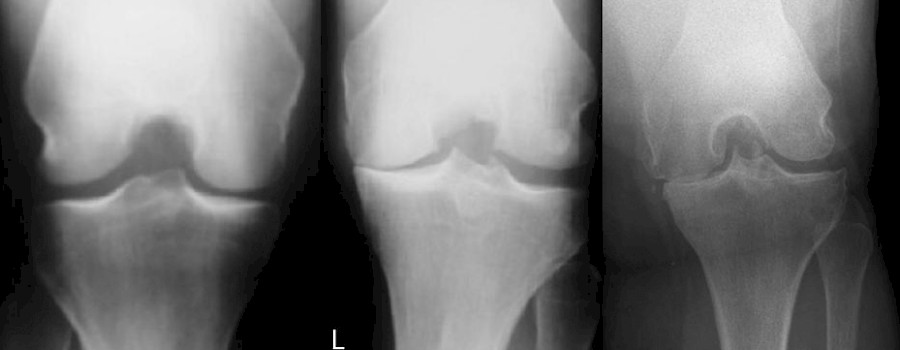

Die „Rosenberg-Aufnahme“ ist eine hilfreiche Alternative zur konventionellen Röntgendiagnostik bei der Kniegelenksarthrose. Die konventionelle radiologische Diagnostik bei der Gonarthrose beinhaltet Belastungsaufnahmen im Stand.